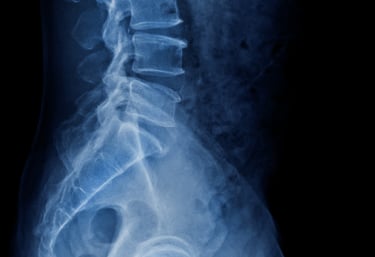

Röntgen, MR & Ultraljud

Kan vara en del av vägen till din diagnos.

Som en del av din utredning på Kroppia gör vi en noggrann klinisk bedömning av om bilddiagnostik är nödvändig för att fastställa rätt diagnos eller säkerställa att behandling kan ske tryggt.

Vi börjar alltid med en grundlig klinisk funktionsanalys. Bilddiagnostik används som ett precisionsverktyg när vi behöver bekräfta fynd eller utesluta bakomliggande orsaker som inte syns vid en manuell undersökning.

Vi går igenom dina röntgen- eller MR-svar tillsammans. Det viktigaste är hur bilderna korrelerar med din biomekaniska status, så att vi kan utforma en träffsäker behandlingsplan.

Tolkning & Åtgärd